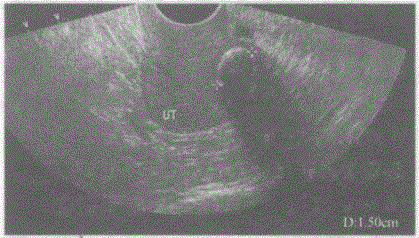

问题 临床资料:女,51岁,绝经2年,常规体检。 超声综合描述:经阴道扫查子宫水平位,测值减小,子宫内膜显示不清,后壁可见低回声,内见直径1.5cm弧形强回声光带,后伴声影。 超声提示:

选项 A.子宫肌瘤并钙化 B.子宫腺肌瘤 C.畸胎瘤 D.子宫腔内异物

答案 A